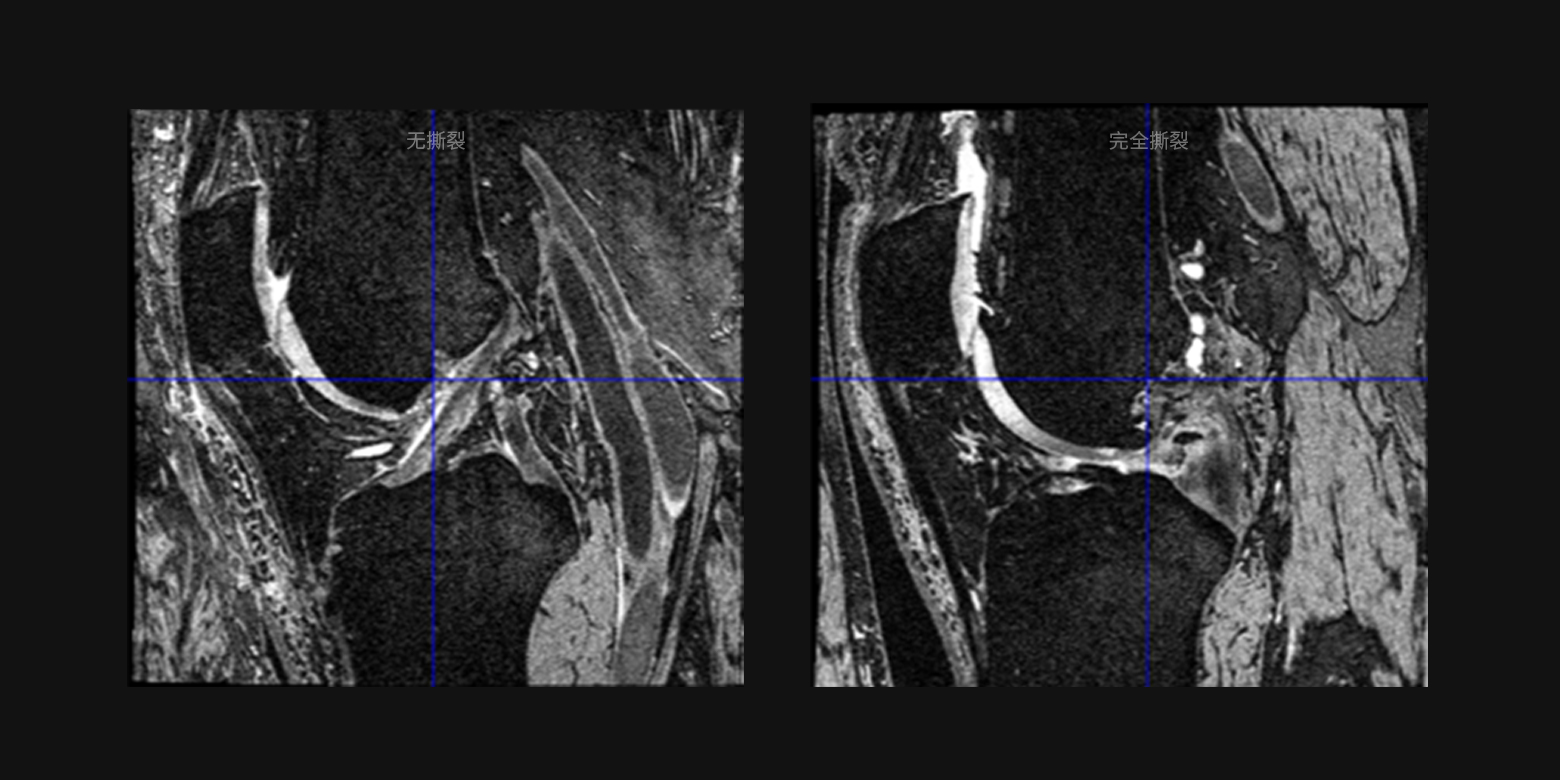

- 03病灶良惡性鑑別和病情分級

03 / 05

病灶良惡性鑑別和病情分級

通過對以往複雜醫學診斷的不斷學習,可滿足大範圍的疾病篩查、病情分級判斷等等的需求,例如可分辨病變是良性或惡性的鑑別,病情的分級,例如十字韌帶撕裂的分級、肺結的惡性鑑別等。

03 / 05

病灶良惡性鑑別和病情分級

通過對以往複雜醫學診斷的不斷學習,可滿足大範圍的疾病篩查、病情分級判斷等等的需求,例如可分辨病變是良性或惡性的鑑別,病情的分級,例如十字韌帶撕裂的分級、肺結的惡性鑑別等。